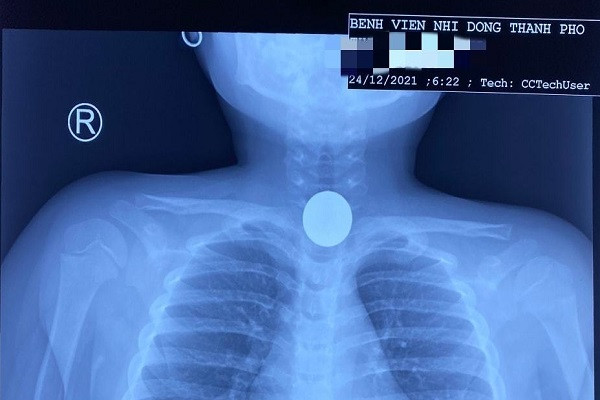

| Hình ảnh chụp Xquang của bệnh nhi. Ảnh: Bệnh viện Nhi đồng Thành phố. |